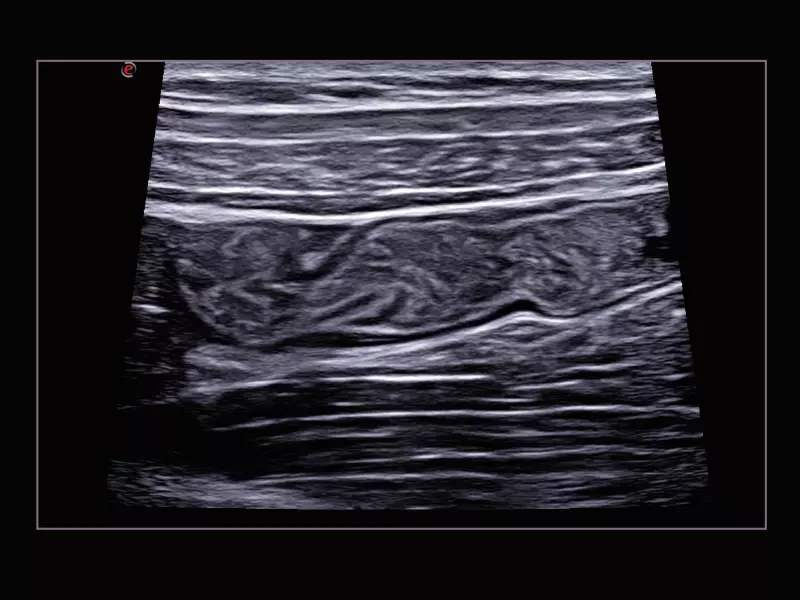

MyLab™Sigma - High Frequency Imaging B-mode of Intestine

MyLab™Sigma - High Frequency Imaging B-mode of Intestine